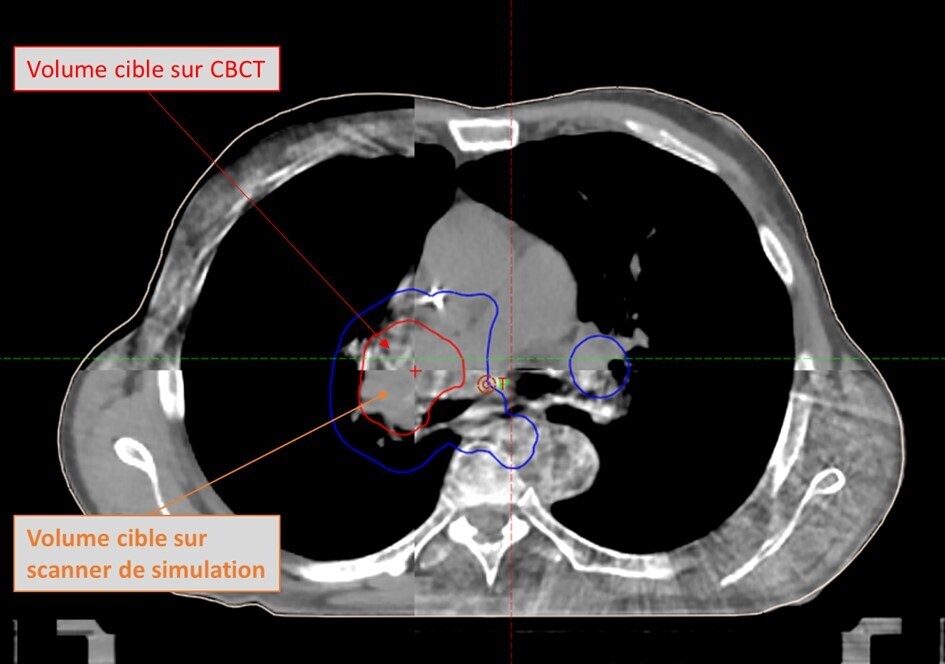

Parmi ces avancées, la tomographie par faisceau conique (CBCT : Cone beam computed tomography) joue un rôle central en réduisant les marges entre le volume cible clinique (CTV) et le volume cible planifié (PTV).1 Cette réduction des marges permet de diminuer la dose au niveau des tissus sains tout en assurant une couverture optimale de la tumeur. Historiquement, la qualité d’image des CBCT classiques était inférieure à celle des scanners pour la planification. Cette limite entravait une délinéation précise des tumeurs et des tissus sains ainsi qu’un calcul optimal des doses. Les technologies CBCT de nouvelle génération (figure) ont considérablement amélioré la qualité d’image en matière de résolution spatiale, de réduction des artefacts et de précision des calculs de dose, rendant ces systèmes désormais adaptés à la personnalisation quotidienne des traitements.15